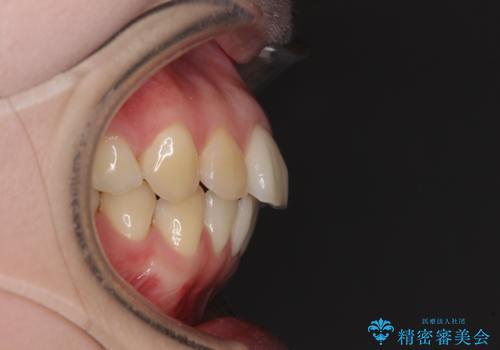

- 高校生の時に矯正治療を行ったものの、後取りをしてしまったとのことで来院された患者様です。

マウスピースでもワイヤー矯正でも対応可能でしたが、再度ワイヤーは装着したくないとのことでインビザラインにて矯正治療を行うこととしました。

舌の突出癖が原因で後戻りをしたため、舌のトレーニングをしっかりと行っていただき、口元の突出感を改善することができました。

インビザラインの装着時間が守れず、1年強で終わる予定でしたが、4年間を要することとなりました。